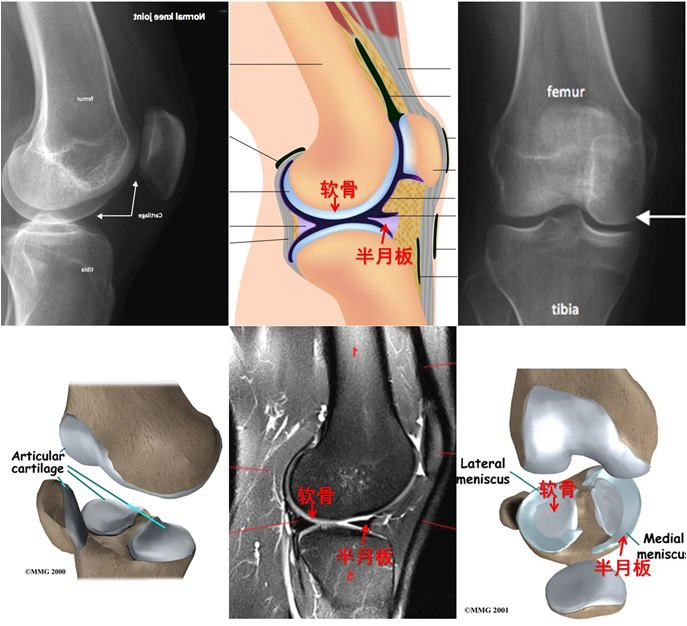

还有一类滑膜炎,是由于反复、大量活动引起的关节软骨损伤、发炎。其中一部分人在就诊之前有各种各样造成关节损伤的原因,常见的有:长距离骑自行车、爬山、旅游、学生体育考试前准备、过度锻炼、走长路,等。从关节面磨损下来的关节碎屑刺激滑膜,引起滑膜增生,分泌关节液,引起关节疼痛、肿胀,形成滑膜炎(图2B)。这种是关节软骨损伤继发的滑膜炎 ,多见于中青年。

图2A.正常的关节:可见关节面软骨(轮胎表面)和半月板(垫片)

图2B.关节软骨损伤继发滑膜炎。过度活动、退变导致关节面软骨损伤(a),产生碎屑(b);碎屑刺激关节腔滑膜,滑膜增生变厚,分泌滑液,关节积液,导致滑膜炎(c)